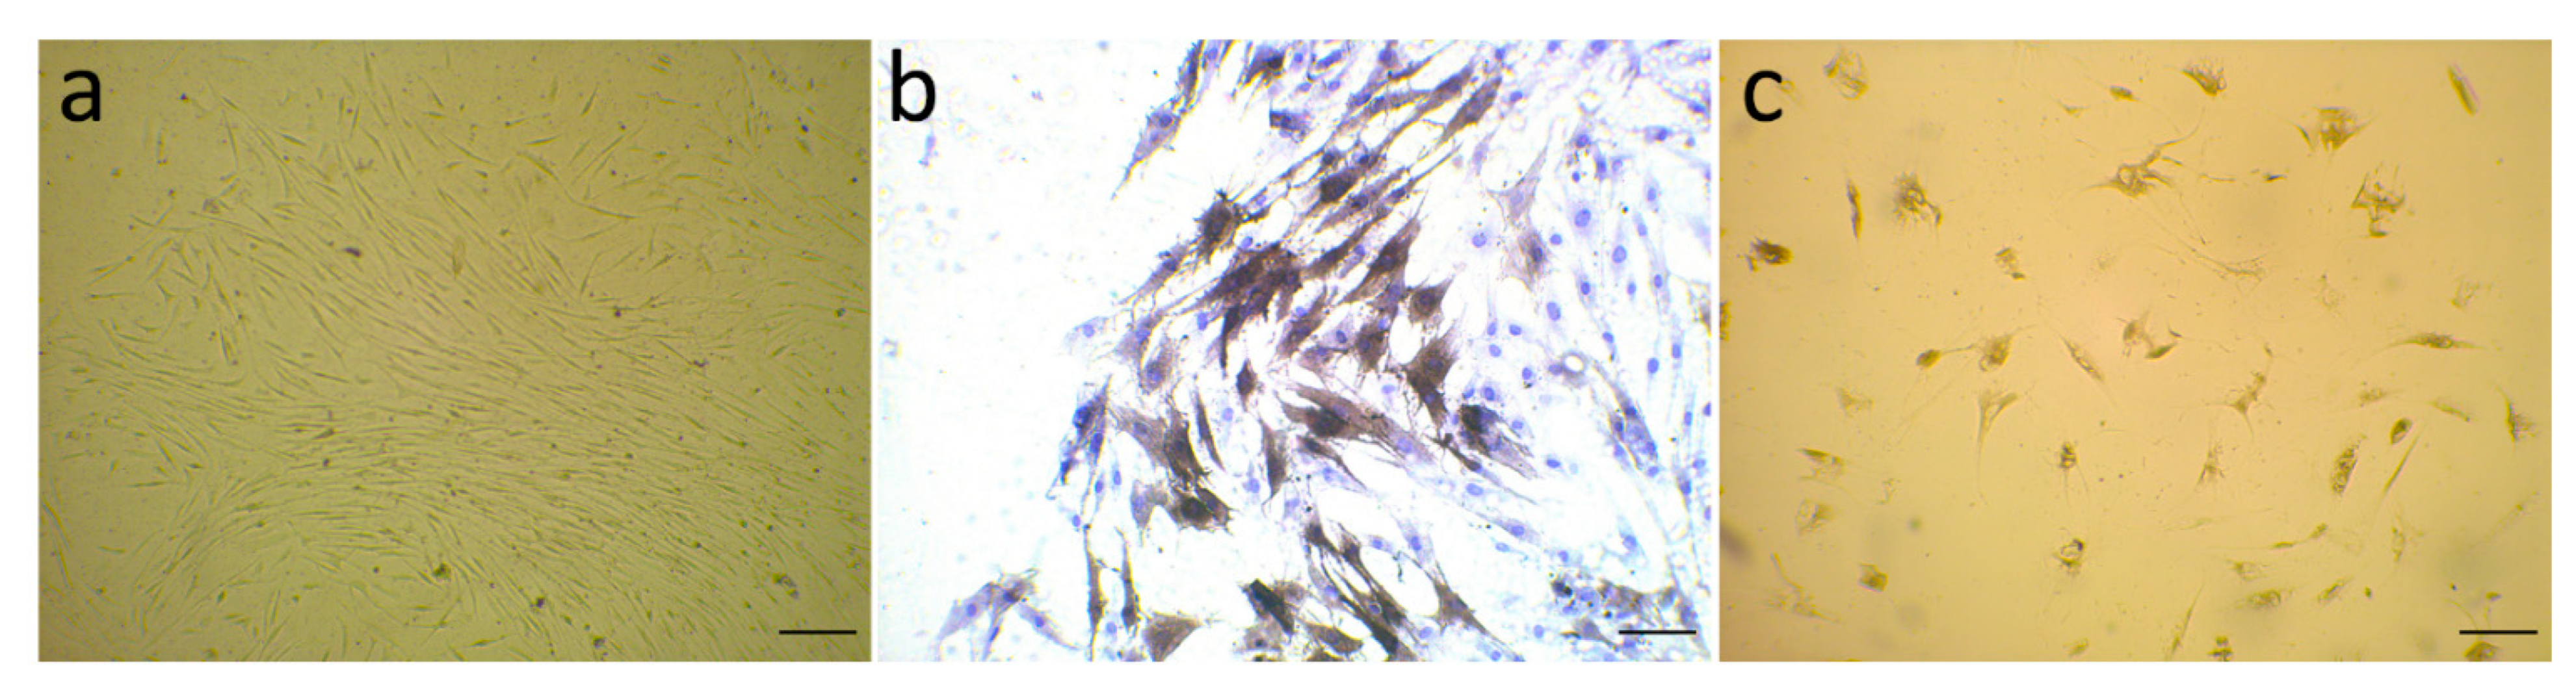

3.1. Evaluation of α-SMA Markers’ Exhibition by Isolated Fibroblast